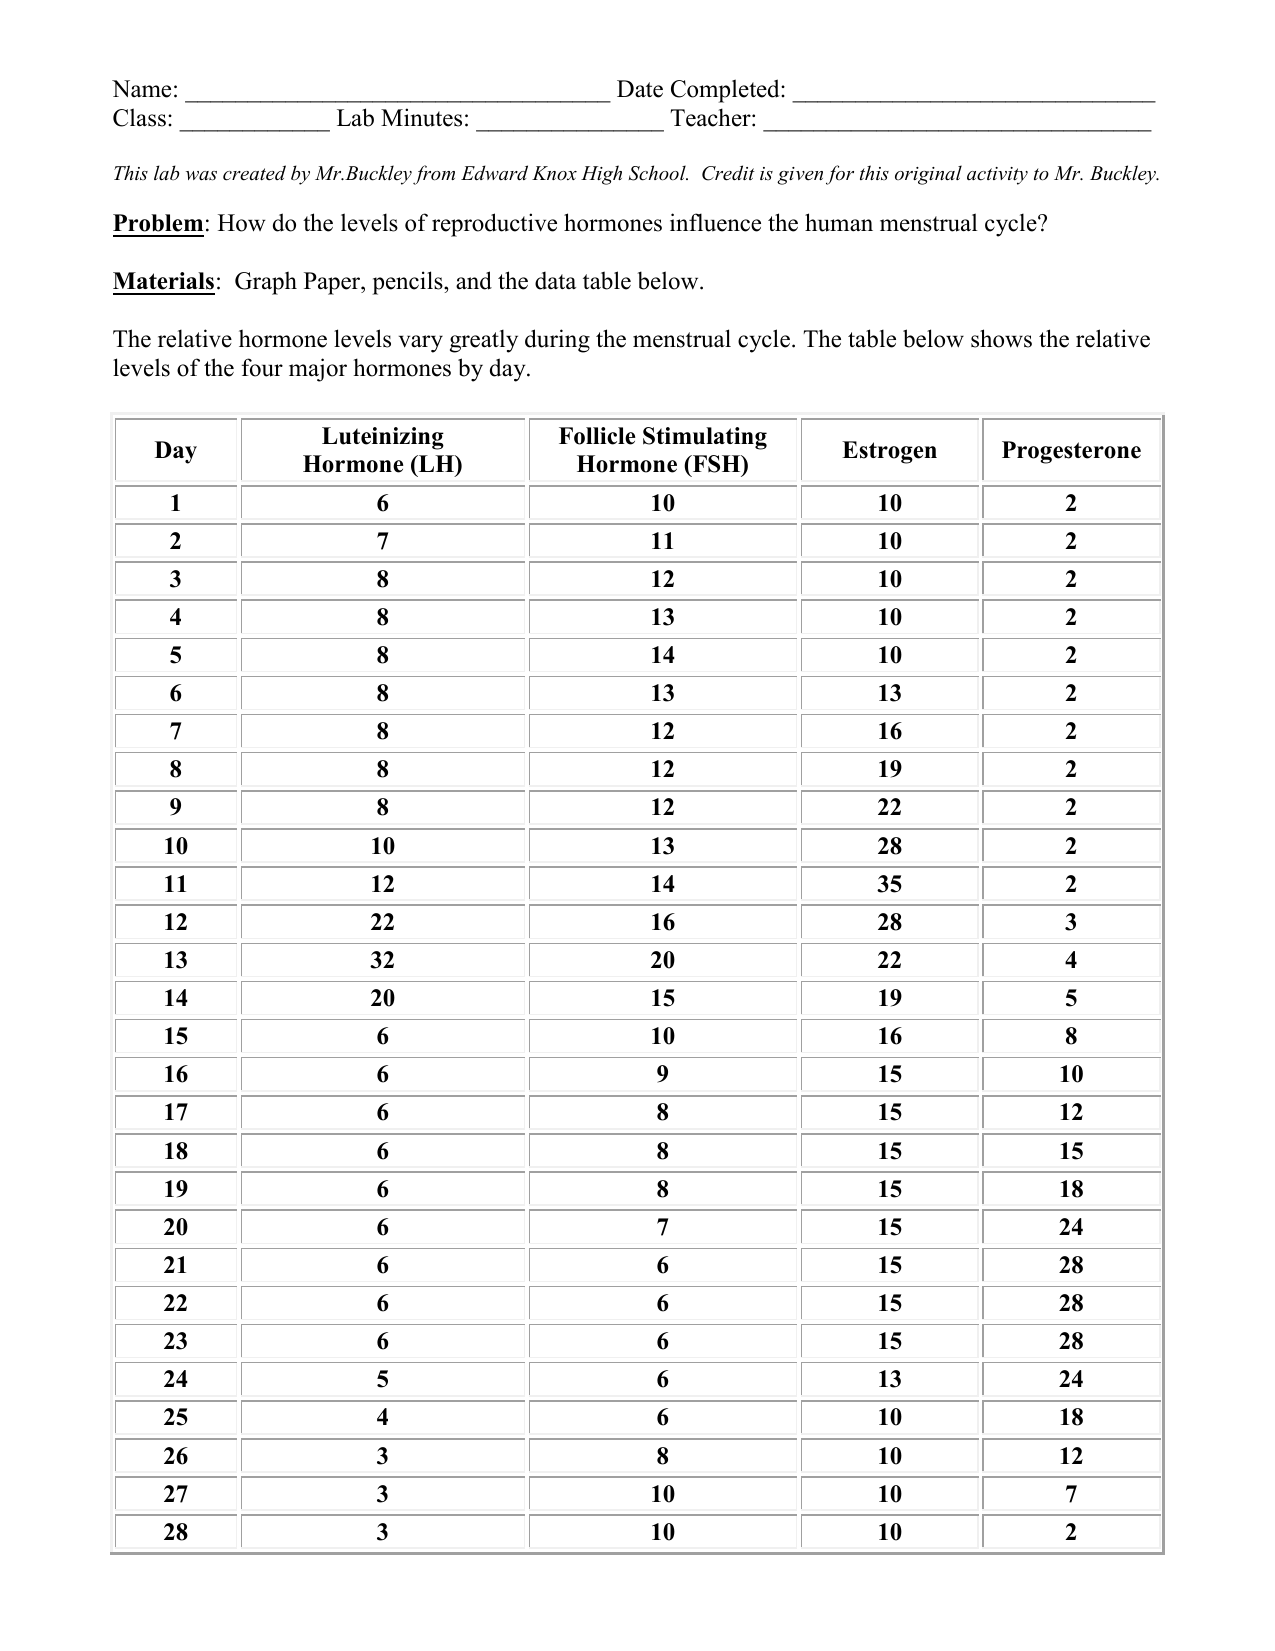

Menstrual Cycle Graphing .

The Menstrual Cycle Assignment A Sixteen Year Old Girls .